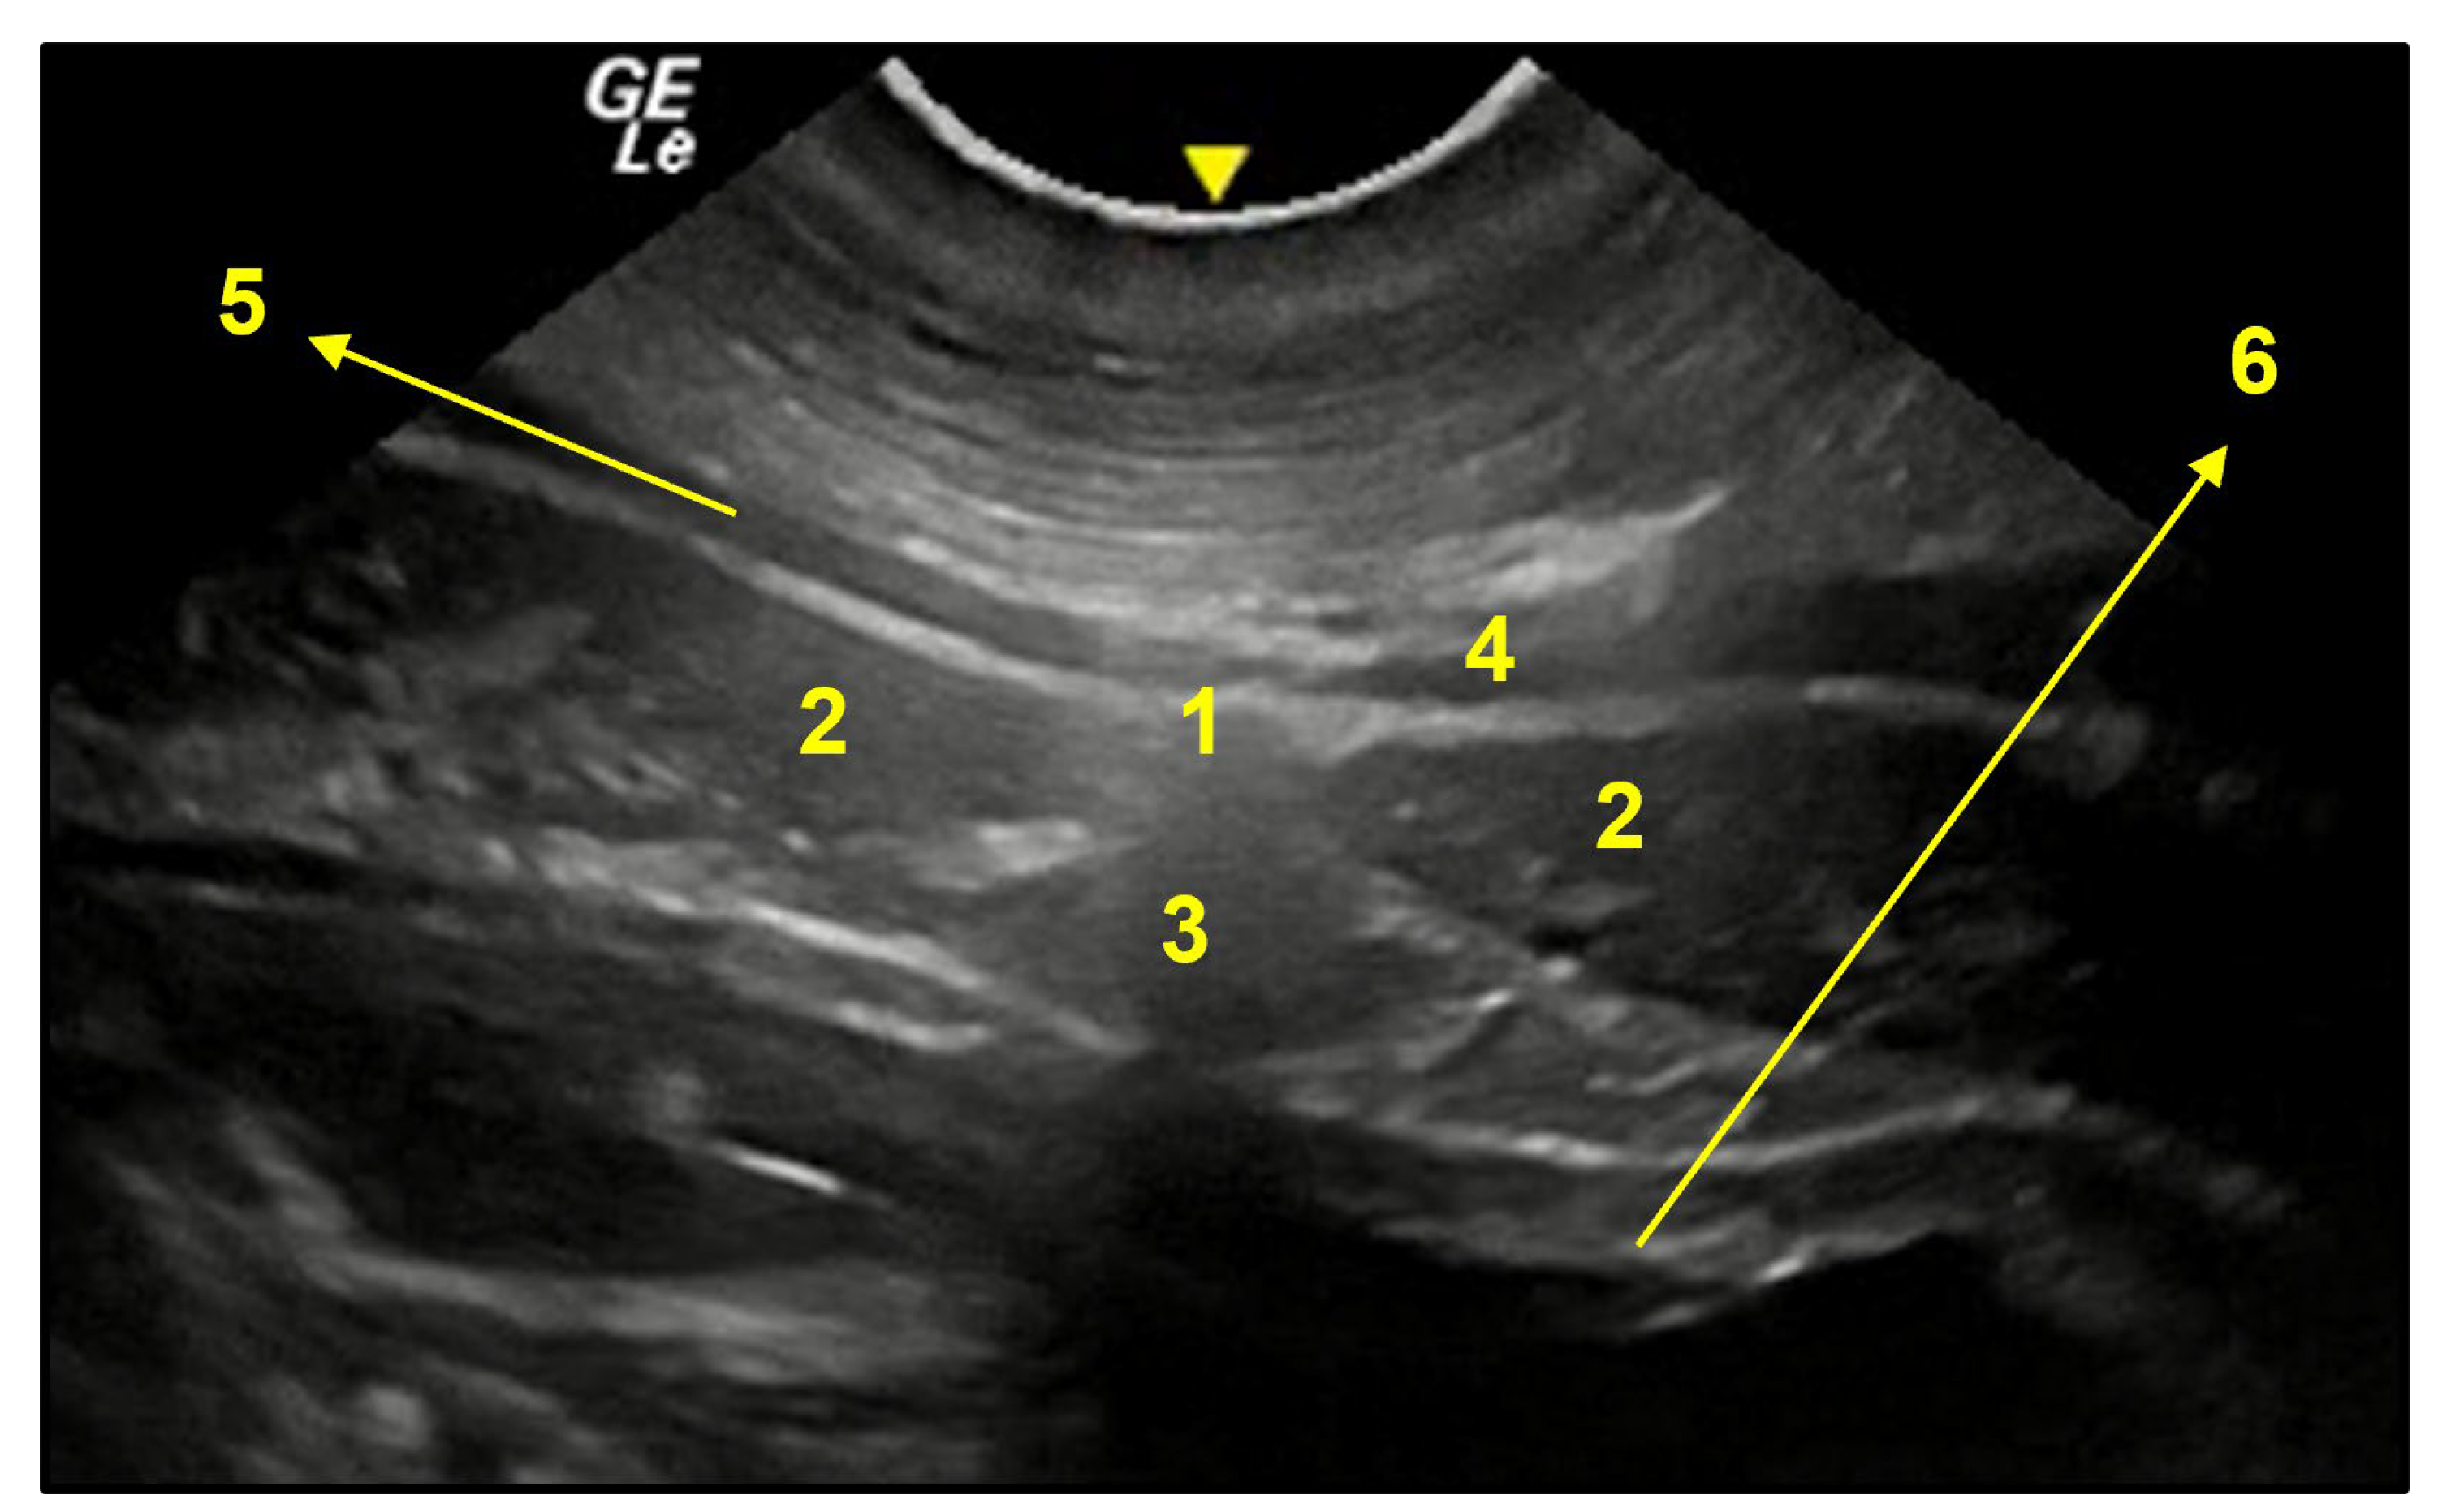

3.3. Ventral Abdominal Ultrasound